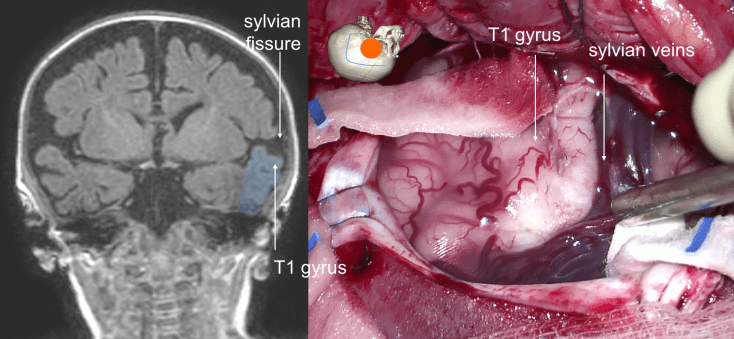

- sous microscope opératoire, incision du gyrus T1 parallèle aux veines sylviennes, coagulation des branches de l’artère sylvienne à destination du pôle temporal

- dissection de la fissure sylvienne, en sous-pial chaque fois que possible de manière à ne pas exposer les branches de l’artère cérébrale moyenne (risque de vasospasme)